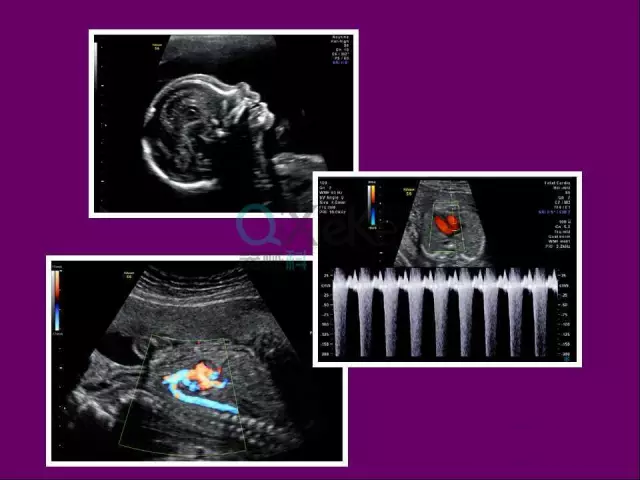

ge彩超s8怎么样中山市宝元医院引进GE Voluson S8 实时四维高端智能彩超_https://www.jmylbn.com_新闻资讯_第2张

智能化分析功能:一键自动测量胎心、羊水、胎盘等关键指标,辅助医生快速评估胎儿发育情况,提升诊断效率。

Code Scan新一代编码技术

新一代数字编码解码技术对超声脉冲进行编码及解码,将数字化超声概念从波束形成器进一步前推到超声波束,多方面提高了超声波图像质量,更为CE(Coded Excitation)编码激励,B-Flow灰阶血流,CHI(Coded Harmonics)编码二次谐波技术,编码造影等一系列临床应用技术提供了基础。